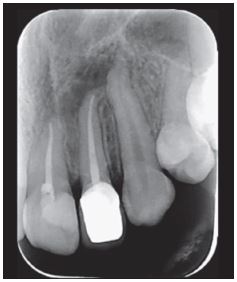

Se indicó una radiografía periapical del diente afectado, con la que se evidenció un área radiolúcida apical y para apical mesial de límites netos y forma redondeada (Figura 1).

Luego se practicó endodoncia en diente 2.2 y diente 2.1 (incisivo central izquierdo); se realizó prótesis fija unitaria en diente 2.2 y se controló radiográficamente a un mes de finalizado el tratamiento endodóncico apreciándose una disminución de la zona radiolúcida (Figura 5).

Al sexto mes posterior al tratamiento, paciente refiere no tener molestia alguna. Se decide controlar con radiografía periapical de diente 2.2, con la que se verifica una disminución notable del área radiolúcida (Figura 6).